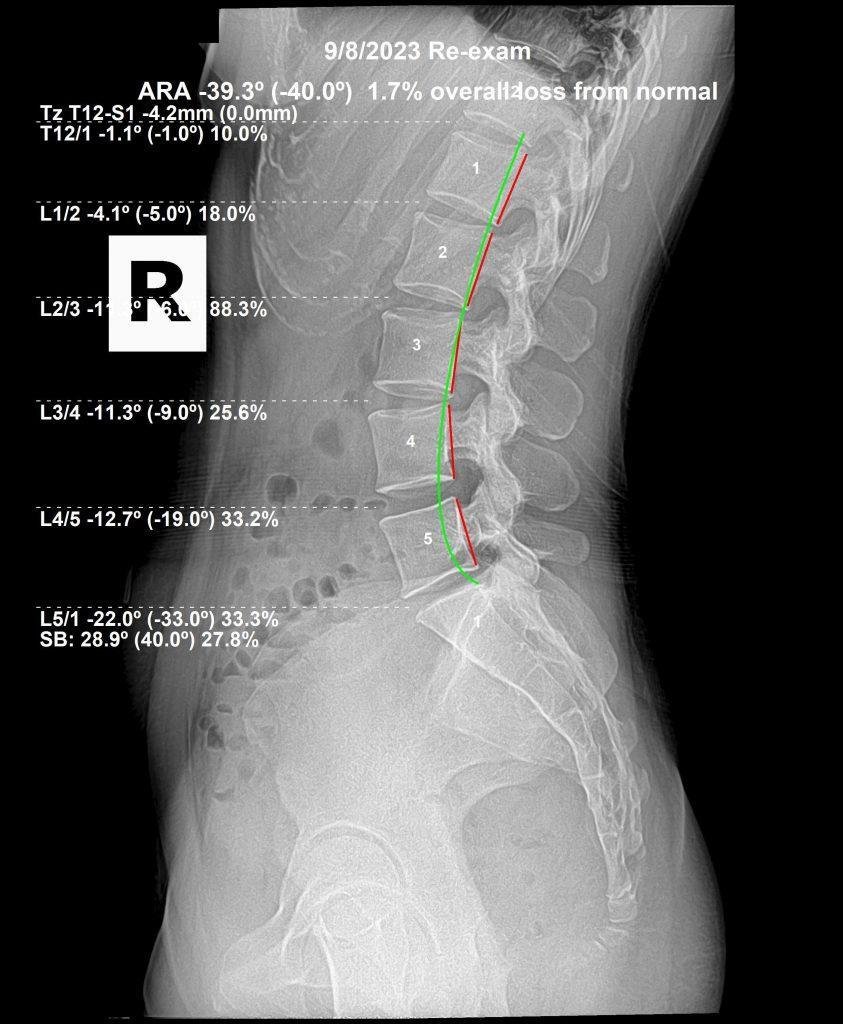

X-ray analysis revealed reversed cervical lordosis, anterior head displacement, and lumbar curve reduction. The before/after X-rays below document the measurable structural change after a structured correction plan.

Before lumbar X-ray — reduced lumbar lordosis Lumbar — Before Lumbar curve reduction visible, contributing to overall postural stress

After lumbar X-ray — dramatic improvement in lumbar lordosis — Dr. Rochet Lumbar — After Dramatic improvement in lumbar lordosis — the body healing globally, not just locally

Actual patient X-rays. Results vary individually.